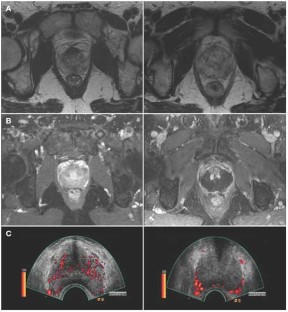

Angiogenesis is an integral part of benign prostatic hyperplasia, is associated with prostatic intraepithelial neoplasia and is a key factor in the growth and metastasis of prostate cancer. This review focuses on ultrasound and dynamic MRI in the evaluation of prostate cancer angiogenesis, and compares these techniques to functional CT and hydrogen magnetic resonance spectroscopic imaging. Image-based evaluation of angiogenesis in the prostate has established clinical roles in lesion detection, tumor staging and the detection of suspected tumor recurrence. One limitation of all these imaging techniques, however, is inadequate lesion characterization, particularly in differentiating prostatitis from cancer in the peripheral zone of the prostate, and in distinguishing between benign prostatic hyperplasia and central-gland tumors. Ultimately, local availability, expertise and the need to minimize patients' radiation burden will influence which technique is used in prostatic evaluations.

Halpern EJ et al. (2001) Prostate cancer: contrast-enhanced US for detection. Radiology 219: 219–225

Frauscher F et al. (2002) Comparison of contrast enhanced color Doppler targeted biopsy with conventional systematic biopsy: impact on prostate cancer detection. J Urol 167: 1648–1652

Unal D et al. (2000) Three-dimensional contrast-enhanced power Doppler ultrasonography and conventional examination methods: the value of diagnostic predictors of prostate cancer. BJU Int 86: 58–64

Ito H et al. (2003) Visualisation of prostate cancer using dynamic contrast-enhanced MRI: comparison with transrectal power Doppler ultrasound. Br J Radiol 76: 617–624

Eckersley RJ et al. (2002) Quantitative microbubble enhanced transrectal ultrasound as a tool for monitoring hormonal treatment of prostate carcinoma. Prostate 51: 256–267